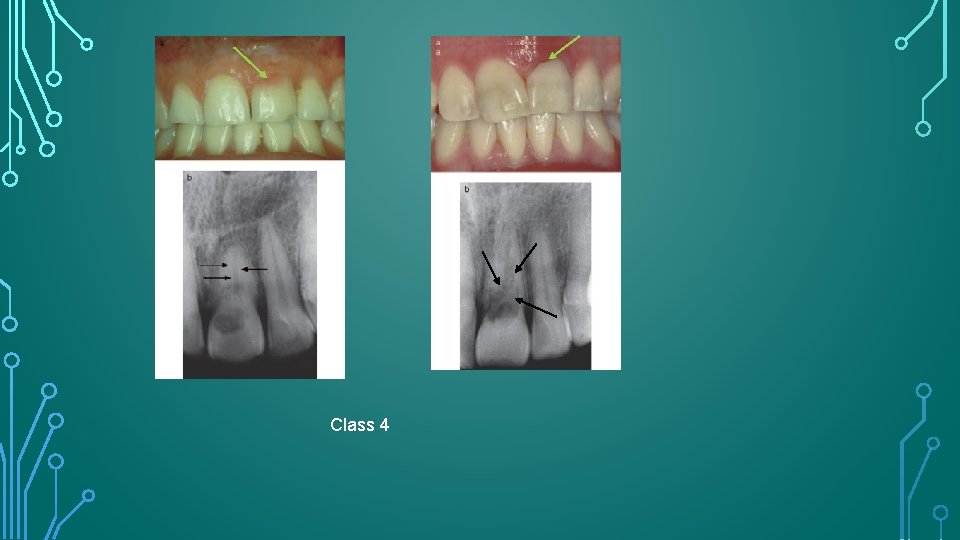

HEITHERSAY CLASSIFICATION FOR ECR • Class 1 –Denotes a small invasive resorptive lesion near the cervical area with shallow penetration into dentine. • Class 2 – Denotes a well-defined invasive resorptive lesion that has penetrated close to the coronal pulp chamber but shows little or no extension into the radicular dentine. • Class 3 – Denotes a deeper invasion of dentine by resorbing tissue, not only involving the coronal dentine but also extending into the coronal third of the root. • Class 4 – Denotes a large invasive resorptive process that has extended beyond the coronal third of the root.

Class 4